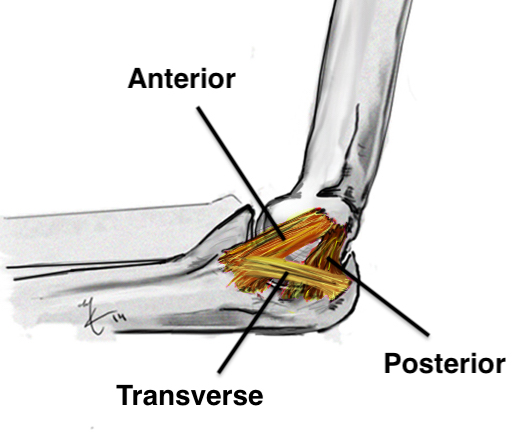

Ligaments

| Lateral collateral ligament | Medial collateral ligament |

| Provides varus stability |

Provide valgus stability in flexion |

| Four components | Three components |

1. Anterior band - most important - medial epicondyle to sublime tubercle

2. Posterior band - medial epicondyle to olecranon

3. Transverse band - olecranon to sublime tubercle - groove for ulna nerve